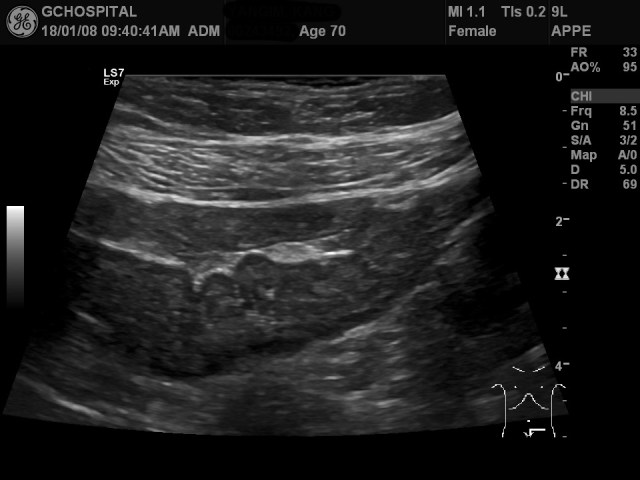

70세 여자환자였고, 며칠동안 지속된 복부전반의 심한 복통을 주소로 응급실에 내원한 후, 기질적인 장내질환들의 가능성을 확인하기 위해 장초음파를 의뢰한 케이스입니다. 장초음파에서 탐촉자를 눌렀을 때 환자가 원래 느끼던 전반적인 복통(pain)에서 좌하복부의 심한 압통(tenderness)으로 증상이 약간 변하면서 해당부위에는 sigmoid colon이 전반적으로 수축되 있으면서 벽두께가 3.0밀리미터정도로 측정되었습니다.

일반적인 대장의 벽두께는 3밀리미터 내로, 장벽의 두께이상은 4밀리미터 이상부터로 정의합니다. 그러므로, 이는 정상수치라고 할수도 있었지만, 압통이 해당부위에 존재했고, 다른 부위의 대장이나 소장의 벽두께보다는 조금 더 두꺼웠다고 판단해서 normal thickness가 아닌 “borderline thickness”가 S결장에 의심되며, infectious, or inflammatory colitis의 가능성을 약하나마 배제하기 어렵다고 판독했었습니다.

환자의 심한 통증의 원인으로 짐작할만한 건 제가 했던 장초음파에서의 S결장의 borderline wall thickening 밖에 없는 상태에서 S결장과 여타 위장관을 추적관찰하기 위해 초음파영상을 찍은 다음날 CT촬영을 한 것이 위 영상입니다.

화살표 부위가 초음파영상에서 보였던 S결장의 수축과 borderline wall thickening을 의심한 부위이지만, CT영상에선 S결장의 수축만 보이고, 벽두께의 증가는 보이지 않습니다. 다른 부위에서도 자궁의 근종외에 다른 이상소견은 안보였습니다.